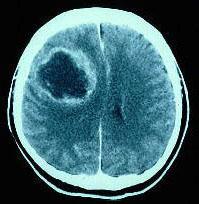

问题 关于脑脓肿(如图所示)的说法,下列哪种是错误的()

选项 A.如进行脓液的细菌检查,一定能发现致病菌 B.先天性心脏病患儿常可并发脑脓肿 C.血源性脑脓肿以额叶顶叶为最多 D.脑脓肿的致病菌以金黄色葡萄球菌最为常见 E.耳源性脑脓肿约2/3发生于患耳同侧的颞叶

答案 A